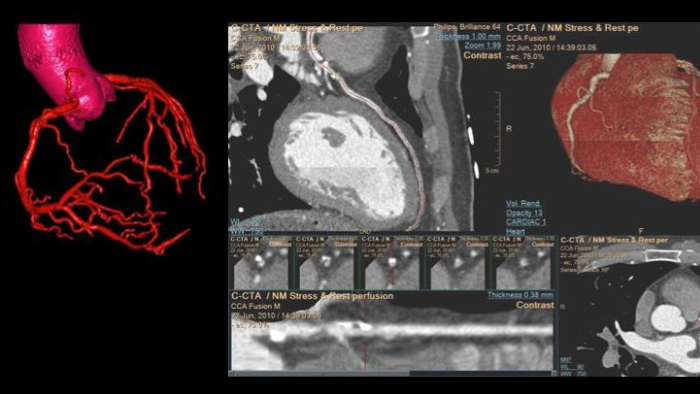

We thank all who were able to attend this year’s European Society of Cardiology programs, including the hands-on workshop sessions, expert symposium on innovations in cardiac imaging workflow, and a friendly open echo skills competition using LifeTec’s Cardiac BioSimulator, the new Philips Compact Ultrasound 5500CV system and Philips Collaboration Live tele-ultrasound.

You can still access recordings of 4 full days of hands-on workshops about best practices in multimodality cardiac imaging with expert teams. See first-time-right imaging for cardiac care, including valvular and related diseases, cardiomyopathies, and intracardiac masses and cardiac tumors.